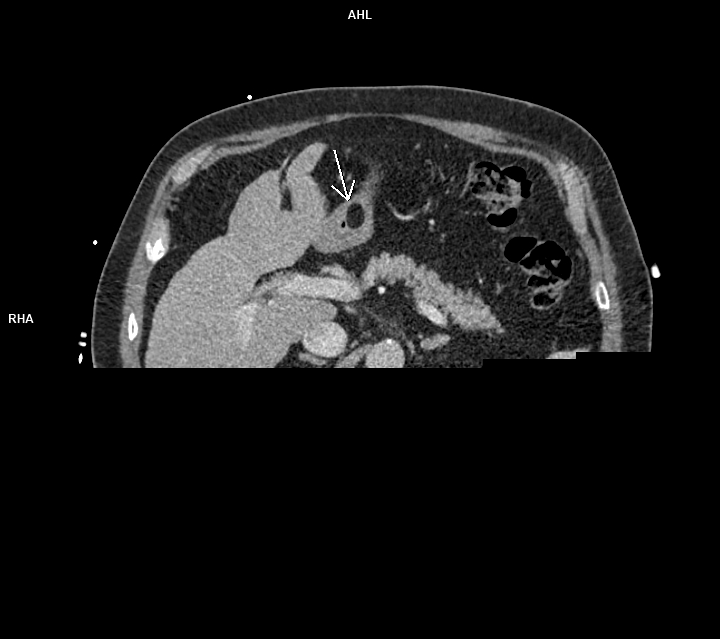

Figura 1: axial CT postcontrast timp venos

Discuţie caz nr 89: lipomul de perete gastric este o tumoră benignă rară de origine mezenchimală ce este, de obicei, descoperire întâmplătoare sub formă unei arii circumscrise cu densități grăsoase ce sunt asimptomatice cand au dimensiuni mici. Sunt de obicei formate din celule grăsoase mature înconjurate de capsulă. Ca și în cazul nostru, sunt întâlnite mai frecvent în antrul gastric. Sunt diagnosticate prin CT deoarece au densități cuprinse între -70 și -120UH .

DE LUAT ACASĂ!!! Lipoamele gastrice sunt cel mai bine diagnosticate prin CT. Septurile fine ale țesuturilor moi probabil indică ulcerații sau modificări post-biopsie; liposarcomul gastric este extrem de rar. IRM-ul poate fi utilizat la copii sau la pacienții radiosensibili; tehnicile CT cu doze mici sunt de asemenea suficiente pentru diagnostic. Lipoamele mai mici de 3 cm sunt asimptomatice. Lipoamele simptomatice mai mari pot fi rezecate endoscopic dacă baza lor este mai mică de 2 cm; rezecția leziunilor cu baze mai largi a fost în mod tradițional retrogradată la rezecția chirurgicală, deși tehnici endoscopice mai noi s-au dovedit eficiente.